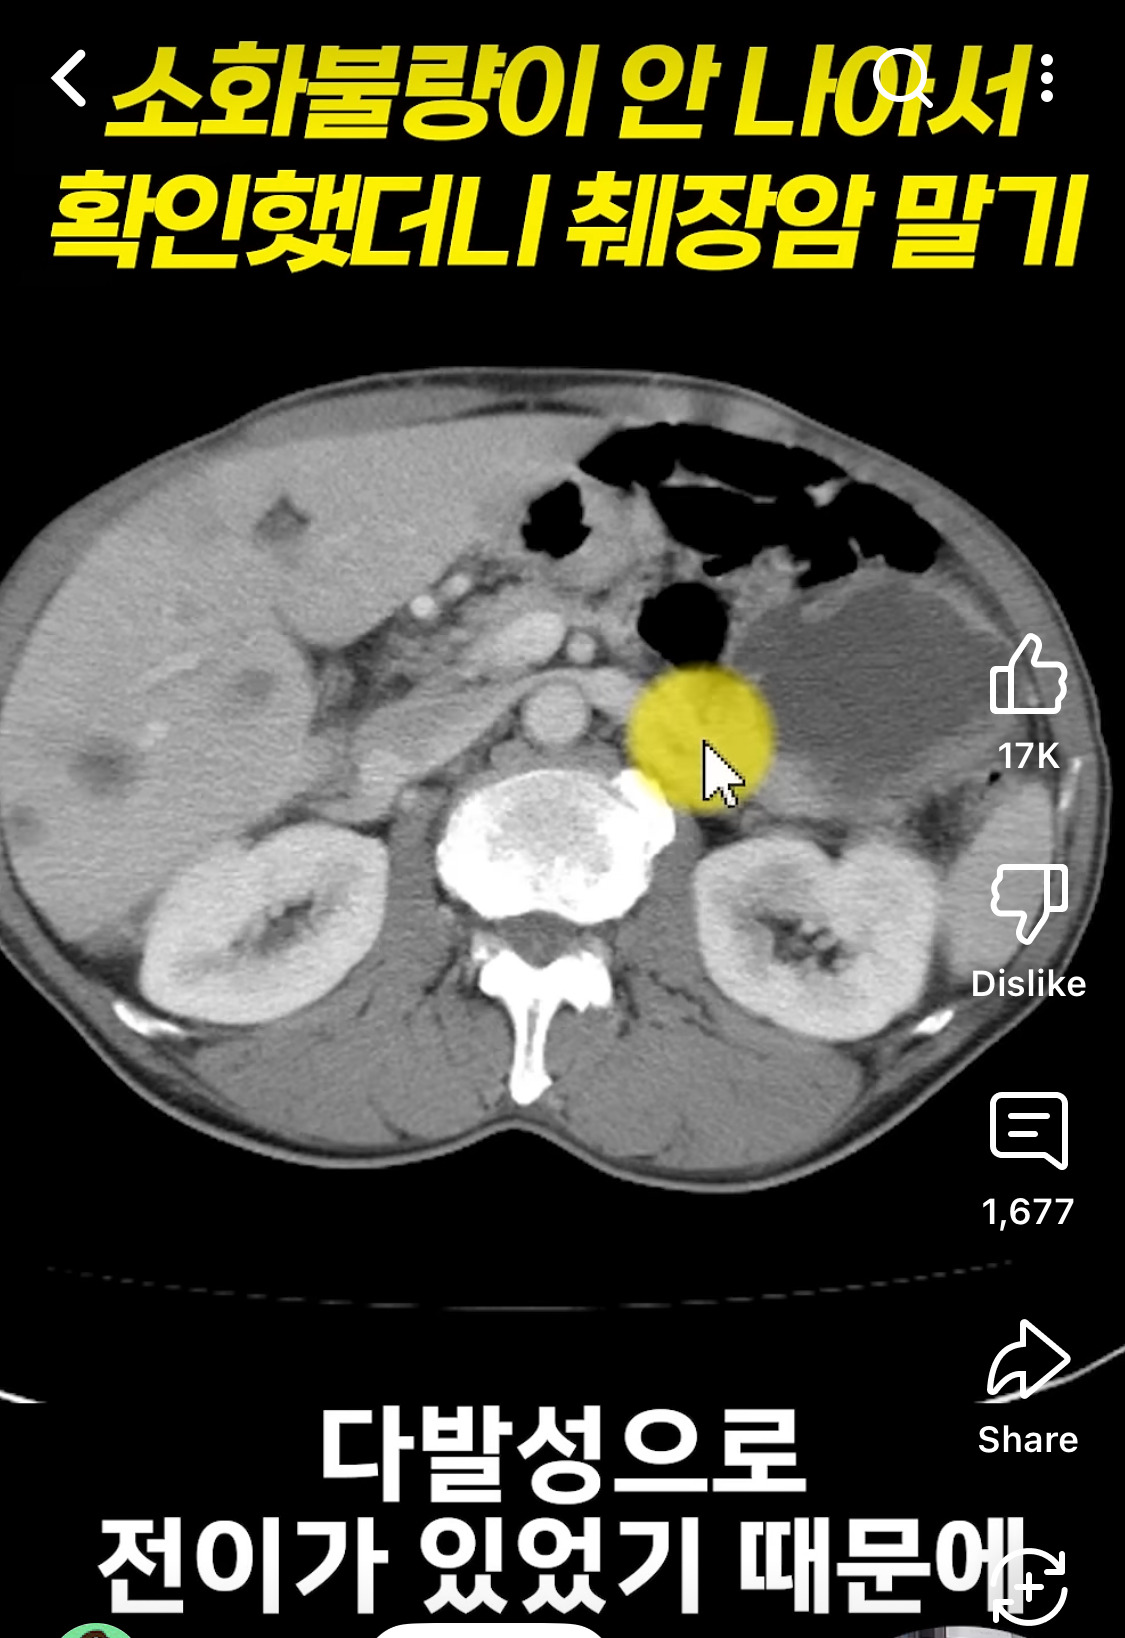

[기타]소화 불량이 안 나아서 확인했더니 췌장암 말기

출처: https://youtube.com/shorts/wkG5O3WpWvY?si=CQgWf196URkjWWMv

부모님들 언제한번 복부 mri 정도는 한번 찍어드리는게 좋음. 방사능 신경안쓰면 씨티해도 되고

참고로 췌장은 위치땜에 초음파로 거의 안보임